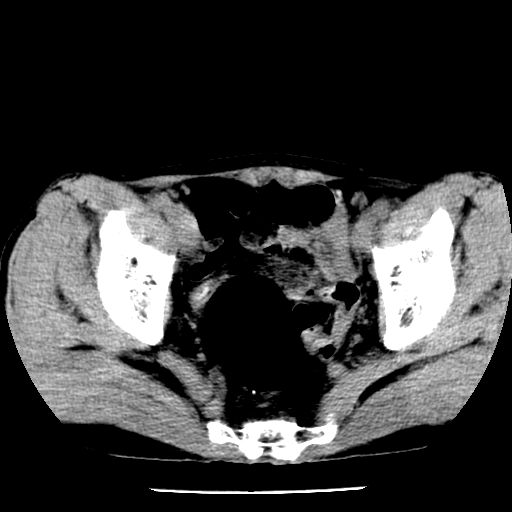

男,59岁,“结核性胸膜炎”30余年,胸部经常疼痛,多次x检查提示“肺部”炎症。腹部疼痛5日,b超提示:“肝内短管结石,余显示不清,建议进一步检查。”

两肺结核并右侧胸腔积液;脾脏、腹腔及腹膜后淋巴结结核[陈旧性];肝内胆管结石

胸部腹部都是结核(双肺。纵隔淋巴结,肝脏,脾脏,肠系膜)

两肺结核并右侧胸腔积液;脾脏、腹腔及腹膜后淋巴结结核[陈旧性];肝内胆管结石。直肠息肉?